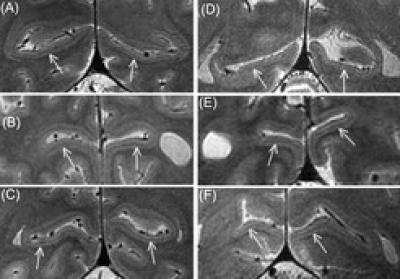

The Stripe of Gennari develops even in those who are blind from birth and does not degenerate, despite a lack of visual input. This was discovered by Robert Trampel and colleagues from the Max Planck Institute for Human Cognitive and Brain Sciences using magnetic resonance imaging. This bundle of nerve fibers, which is approximately 0.3 mm thick, is not exclusively responsible for optic information. In the blind, it might play a greater role in processing tactile stimuli. This could contribute to an enhanced sense of touch and support fast reading of Braille. ( Cerebral Cortex , Online 10. 02. 2011)

The Stripe of Gennari – also known as the 'Stria of Gennari' – transverses the gray matter of the primary visual cortex as a distinct white line. "Although the visual cortex is one of the best-studied parts of the brain, and the Stripe of Gennari is a rather obvious structure, why it develops and what its function is has not previously been studied in detail", explains Robert Trampel from the Max Planck Institute for Human Cognitive and Brain Sciences. "An obvious connection with sight was assumed."

However, as is now clear, this cannot be the only function of the stripe of Gennari: In a functional magnetic resonance imaging (fMRI) study, the researchers found the stripe of Gennari in the brains of congenitally blind subjects. "This brain structure therefore can't exclusively be involved in vision and must be capable of carrying out other tasks", says Trampel. In the blind, the Stripe of Gennari could play a role in supporting the sense of touch, the scientists speculate. "This faculty is essential in reading Braille and the region carrying the Gennari-Stripe is known to show an increased activity in the blind when performing this task." All participants in the present study were highly proficient in reading Braille, having responded to an advertisement written in Braille in a newspaper for the visually impaired.